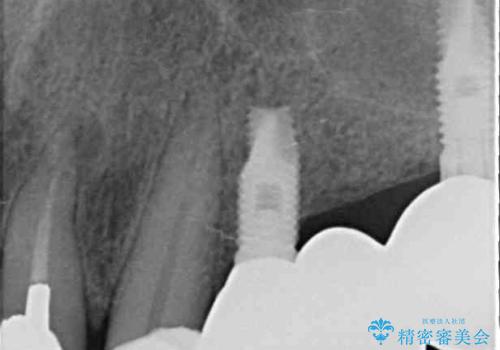

- 上の奥歯に装着されているブリッジが痛むとのことで来院された患者様です。

診察した結果、ブリッジの土台となっている歯が割れていたため、抜歯が必要となりました。

欠損している歯数が多いため、ブリッジによる補綴治療は困難と判断し、インプラントによる補綴治療を行うこととしました。

インプラントを埋入するために必要な骨の高さがなかったため、上顎洞底の粘膜を挙上しました。